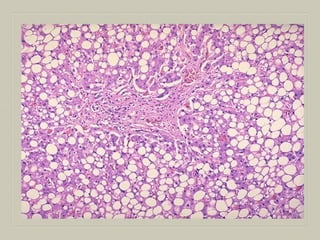

MICROSCOPY

 Fat in the cytoplasm of the hepatocytes is seen as

clear area which may vary from minute droplets in the

cytoplasm of a few hepatocytes [microvesicular] to

distension of the entire cytoplasm of most cells by

coaslesced droplets [macrovesicular] pushing the

nucleus to the periphery of the cell.

 Occ. the adjacent cell containing fat, rupture

producing fatty cysts

 Special stains such Sudan III & IV,Sudan black Oil

red O can be employed to demonstrate fat in the

tissue

MICROSCOPY  Fat inthe cytoplasm of the hepatocytes is seen as clear area which may vary from minute droplets in the cytoplasm of a few hepatocytes [microvesicular] to distension of the entire cytoplasm of most cells by coaslesced droplets [macrovesicular] pushing the nucleus to the periphery of the cell.  Occ. the adjacent cell containing fat, rupture producing fatty cysts  Special stains such Sudan III & IV,Sudan black Oil red O can be employed to demonstrate fat in the tissue